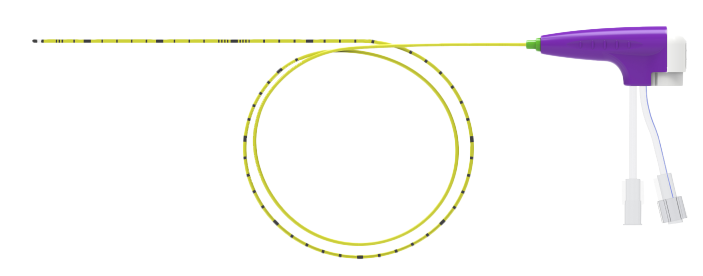

Reliable Needle Bar Strength

Needle bar designs of various lengths meet various puncture depths

Reinforced sharp needle for easy puncture

Different handle designs meet different guiding methods

A variety of long and short needle designs to meet the needs of clinical applications